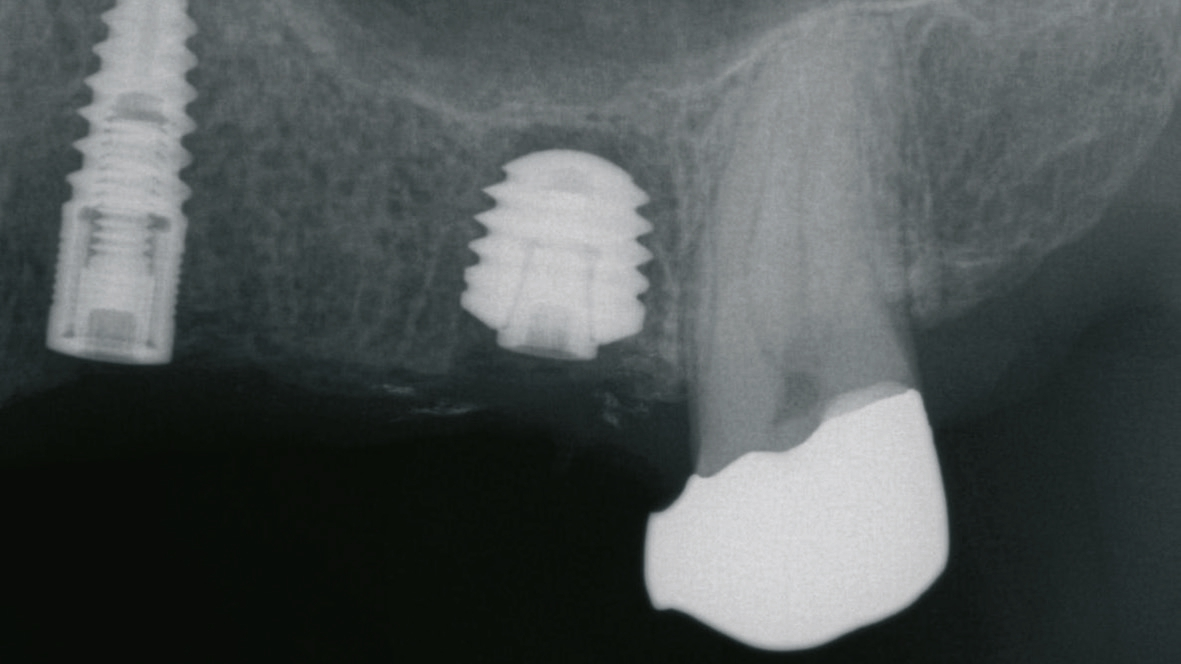

Beim Fehlen von mehreren Zähnen können unterschiedliche Planungs- und Versorgungskonzepte zur Anwendung kommen. Zur Kompensation der geringeren Verankerungsfläche von kurzen Implantaten im Knochen wird neben der Zahn-für-Zahn-Versorgung eine Verblockung von multiplen Implantaten empfohlen [6]. Die Empfehlungen sind aber im Kontext der jeweiligen Implantat- Aufbau-Verbindung, die bei der Versorgung von kurzen Implantaten zur Anwendung gekommen ist, zu berücksichtigen. Aus dem Anwendungsbereich der Implantate mit einer externen Implantataufbauverbindung wird eine Verblockung angeraten, um eine ausreichende Stabilität besonders bei einer hohen Aufbauhöhe des Zahnersatzes sicher zu stellen [6]. Die Erfahrung bei der Anwendung von Implantaten mit einer konischen Implantataufbauverbindung hat gezeigt, dass sich multiple Einzelkronen langzeitstabil eingliedern lassen [2] (Abb. 9-14). Besonders in Hinblick auf das periimplantäre Knochenniveau wird davon ausgegangen, dass sich bei der Einzelversorgung keine Spannungen auf Grund einer unzureichenden zahntechnischen Herstellungsgenauigkeit ergeben können.

Zeigt sich im Rahmen der Planung, dass das vertikale Knochenangebot nur in einem Bereich des zahnlosen Kieferkammabschnittes vorliegt, können kurze Implantate auch mit längeren Implantaten kombiniert werden. Dann kann anstelle der multiplen Einzelversorgung auch eine Brückenversorgung angegangen werden (Abb. 15-18). Bei der Verblockung von Implantaten mit einer konischen Implantataufbauverbindung muss auf eine genaue Übertragung der Implantatanschlussgeometrie geachtet werden, da es durch die Toleranzen bei der Herstellung des Konus zu einem vertikalen Versatz kommen kann. Im Vergleich zu Implantaten mit einer zylindrischen, parallelen Verbindung fehlt hier der Anschlag, der eine genaue Übertragung der vertikalen Position sicherstellt. Um diesen vertikalen Fehler zu vermeiden empfiehlt es sich auf Abutmentniveau abzuformen. In diesem Fall kann das Abutment auch in-situ verbleiben, so dass das periimplantäre Weichgewebe nicht mehrfach traumatisiert wird.